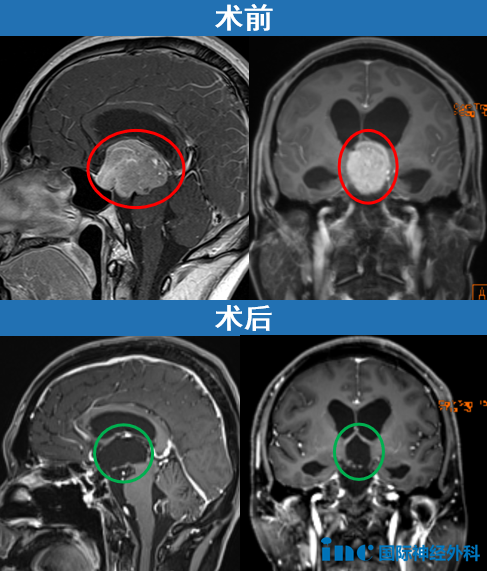

2025年6月,35岁的江先生发现鞍区及鞍上的巨大垂体瘤引发阻塞性脑积水。巨大肿瘤早已压迫到脑干、第三脑室及导水管。“手术风险太大,难度这么高,你们还是去其他地方看看吧……”

不放弃之下,他们迎来转机。没有开颅,INC福教授在北京天坛医院最终通过经鼻内镜手术成功切除了这个巨大的垂体瘤。